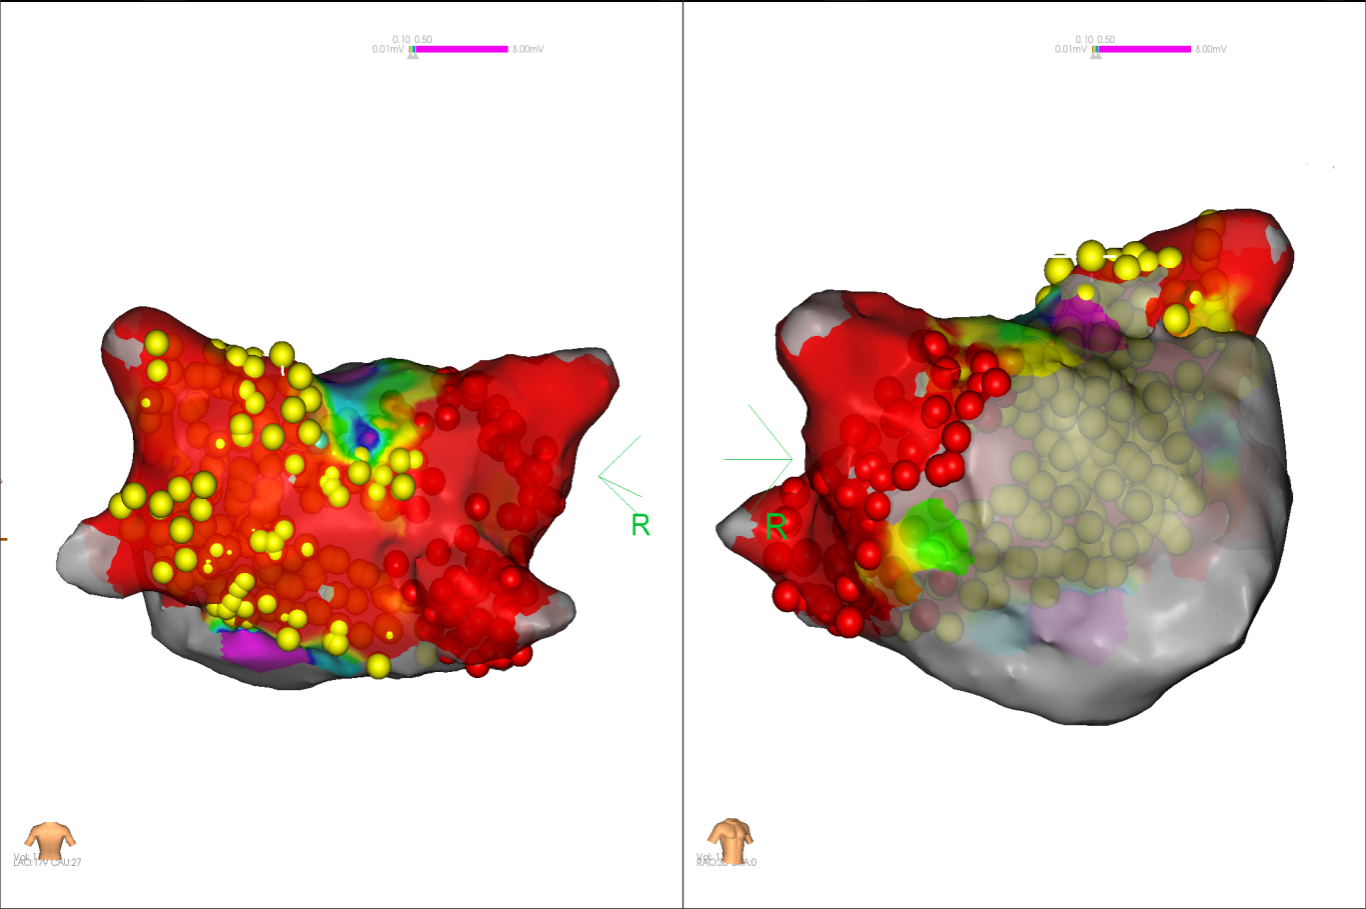

图2 术中电压标测提示左房基质差

图4 消融前后基质标测提示肺静脉消融效果明显

经充分术前评估及准备后,该患者手术在抗心衰药物持续静脉泵入、高流量吸氧支持下及麻醉、护理团队的通力配合下进行,由薛建颖、崔明亮主治医师具体实施。术中通过右侧股静脉送入心腔内超声至右心房,排除左房血栓后成功指导房间隔穿刺,沿可调弯鞘管送入锦江心脏脉冲电场消融导管至左房,构建左房三维解剖模型并行基质标测,标测显示左房基质差,分别行左侧、右侧肺静脉及后壁BOX消融。消融参数:1800v,400ms,400μs,共放电消融140次(消融右肺静脉时转复为窦性心律),验证双肺静脉均隔离。术后重新标测显示所有肺静脉均已急性阻滞,消融效果理想,肺静脉前庭损伤范围也达到了预期的标准,同时心腔内超声监测未见明显心包积液。手术仅用时30分钟,时间明显缩短,手术过程精准高效。术后患者恢复情况良好,维持窦性心律。